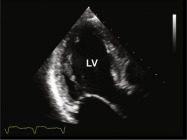

| 2.15. Mặt cắt 4 buồng từ mỏm phóng đại hình ảnh thất trái |

Cửa sổ siêu âm từ mỏm tim

Mặt cắt 4 buồng Điều chỉnh depth để khu trú vào hình ảnh thất trái |

Thất trái (LV) | |||||